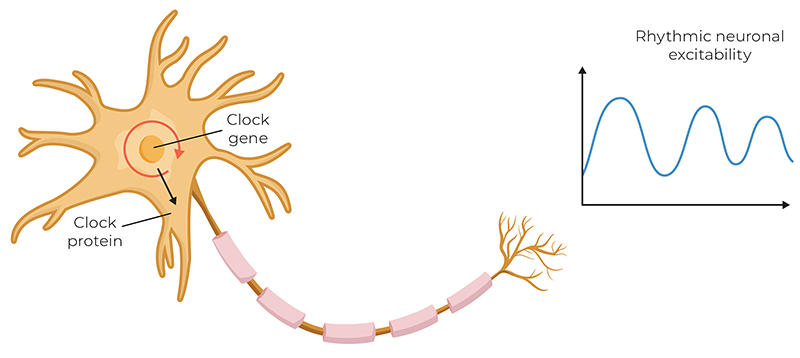

To understand CSR better, we can look at another one of the body’s most important rhythms. The 2017 Nobel Prize in Physiology or Medicine was awarded to Jeffrey C. Hall, Michael Rosbash, and Michael W. Young for their work describing the molecular mechanisms of the circadian rhythm. All aspects of our organs and cellular functions are governed by circadian rhythms, the most obvious being our sleep-wake cycle. The biological clock’s cycle is generated by a feedback loop, in which genes are activated that trigger the production of proteins. As protein levels build to a critical point, the genes are switched off. Over time, the proteins degrade to a level that allows the genes to switch back on, restarting the cycle.

The pacemaker for the circadian rhythm is in the hypothalamus, near the third ventricle of the brain. This pacemaker generates an internal representation of solar time that is conveyed to every cell in the body, coordinating the daily cycles of physiology and behavior. Today, there is growing recognition that chronic disruption of circadian rhythms has profound effects on our health. Is there a link between what we’re learning about the pacemaker of the circadian rhythm and CSR?

The Pacemaker Theory positions the CSR as one of several neurogenic rhythms—autonomously generated patterns of electrical activity produced by networks of oscillating neurons located in the brain stem near the fourth ventricle.11 These neurons act as central pacemakers, producing rhythmic discharges independent of respiration or cardiac rhythms. The autonomic nervous system integrates multiple physiological systems and serves as a critical conduit for communication between a central pacemaker in the brain stem and peripheral oscillators in vascular structures.

Oscillating neurons in the central and peripheral nervous systems create self-sustaining rhythmic patterns through intrinsic properties and synaptic architecture. These neural oscillators generate rhythms critical for survival, underpinning vital autonomic and cognitive functions such as locomotion, sleep, and breathing. Recent models show that rhythmic behaviors emerge not from a single neuron but from networks of oscillators synchronizing over time—what researchers call network synchrony. They arise from interactions involving excitatory and inhibitory circuits, ion channels, and gap junctions.18 Tools such as EEG, MEG, and local field potentials enable detection and study of these rhythms. Though difficult to isolate to single neurons, modern neuroscience identifies regions where rhythm generation occurs and tracks how they influence bodily systems.19 Dysfunction in synchronization can lead to disorders such as arrhythmia, Parkinson’s disease, or sleep disorders. Computational neuroscience continues to explore how these rhythms arise, interact, and relate to body systems, offering insight into how rhythms—like the CSR—can potentially affect global physiology.20